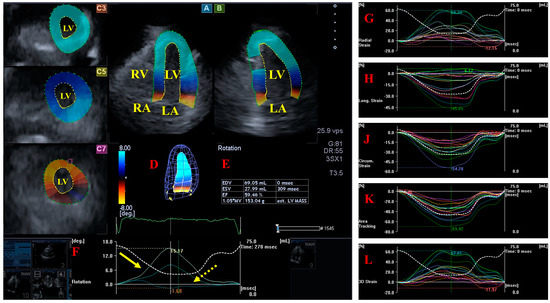

- Nemes, A.; Földeák, D.; Domsik, P.; Kalapos, A.; Sepp, R.; Borbényi, Z.; Forster, T. Different patterns of left ventricular rotational mechanics in cardiac amyloidosis-results from the three-dimensional speckle-tracking echocardiographic MAGYAR-Path Study. Quant. Imaging Med. Surg. 2015, 5, 853–857. [Google Scholar] [PubMed]